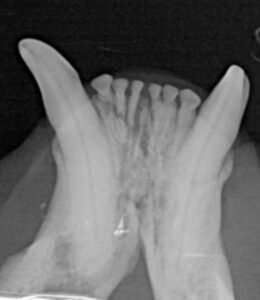

Dental Disease Often Occurs Below the Gumline

Many serious dental problems occur below the gumline where they cannot be seen during a routine visual exam. Teeth may appear normal above the gumline while significant infection or bone loss is present beneath the surface.

Left Photo: Dental probe, which has marks that measure pockets caused by dental disease below the gumline. It should not be able to go more than 2-3mm or lines below the gumline.

Right Photo: The same probe inserted into a deep periodontal pocket behind a canine tooth. The tooth appeared normal externally, demonstrating why probing and dental imaging are critical to diagnosing periodontal disease.